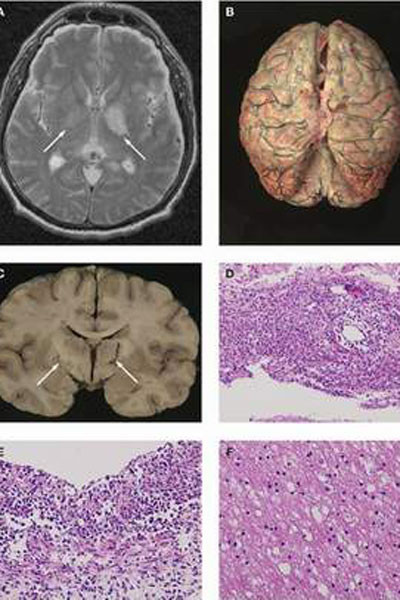

Ban đầu, vi trùng não mô cầu hay còn gọi là màng não cầu khi vào cơ thể sẽ gây viêm họng- mũi, nếu sức đề kháng tốt thì sẽ tự khỏi. Khi cơ thể yếu, vi trùng tiếp tục lan vào máu đi khắp cơ thể gây nhiễm trùng huyết, viêm màng não và có thể tử vong một cách nhanh chóng. Đặc biệt, trong thể nặng, bệnh nhân nhiễm trùng huyết tối cấp, tỷ lệ tử vong rất cao (từ khi diễn tiến bệnh cho đến lúc tử vong chỉ trong vòng một ngày). Những bệnh nhân may mắn thoát chết sẽ mang những di chứng nghiêm trọng như phải cắt bỏ các chi, tổn thương não, giảm thính lực, tổn thương thận và các vấn đề tâm lý. Do đó, theo bác sĩ Chính, khi có biểu hiện viêm họng, kèm theo phát ban mụn đỏ, bệnh nhân cần đưa đến bệnh viện ngay để được các bác sĩ can thiệp kịp thời, khoanh vùng lây lan, cách ly người bệnh.